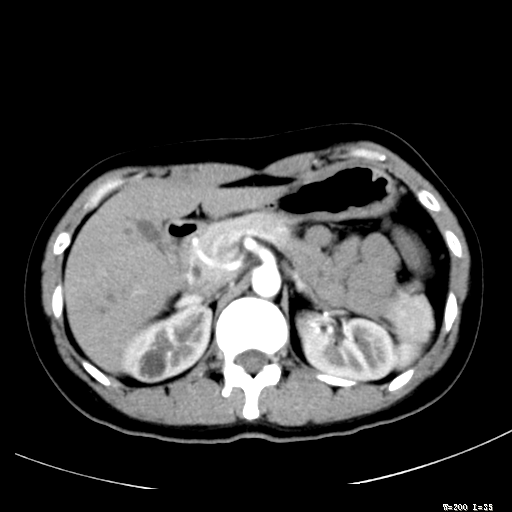

标题: CT25345:右肾占位。

女,30岁,右腰部胀痛3个月。

增强无明显强化,先考虑血管平滑肌脂肪瘤,建议作薄层扫描右mri检查,

感觉像囊肿.

囊肿!

考虑右肾近上极囊肿;建议必时行mri检查。